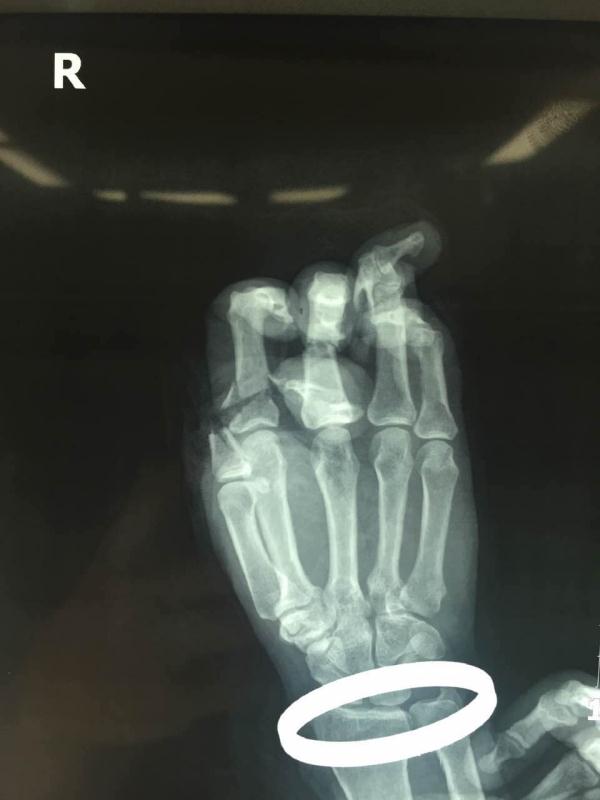

患者的左右手X光片:9指被切断,情势危急